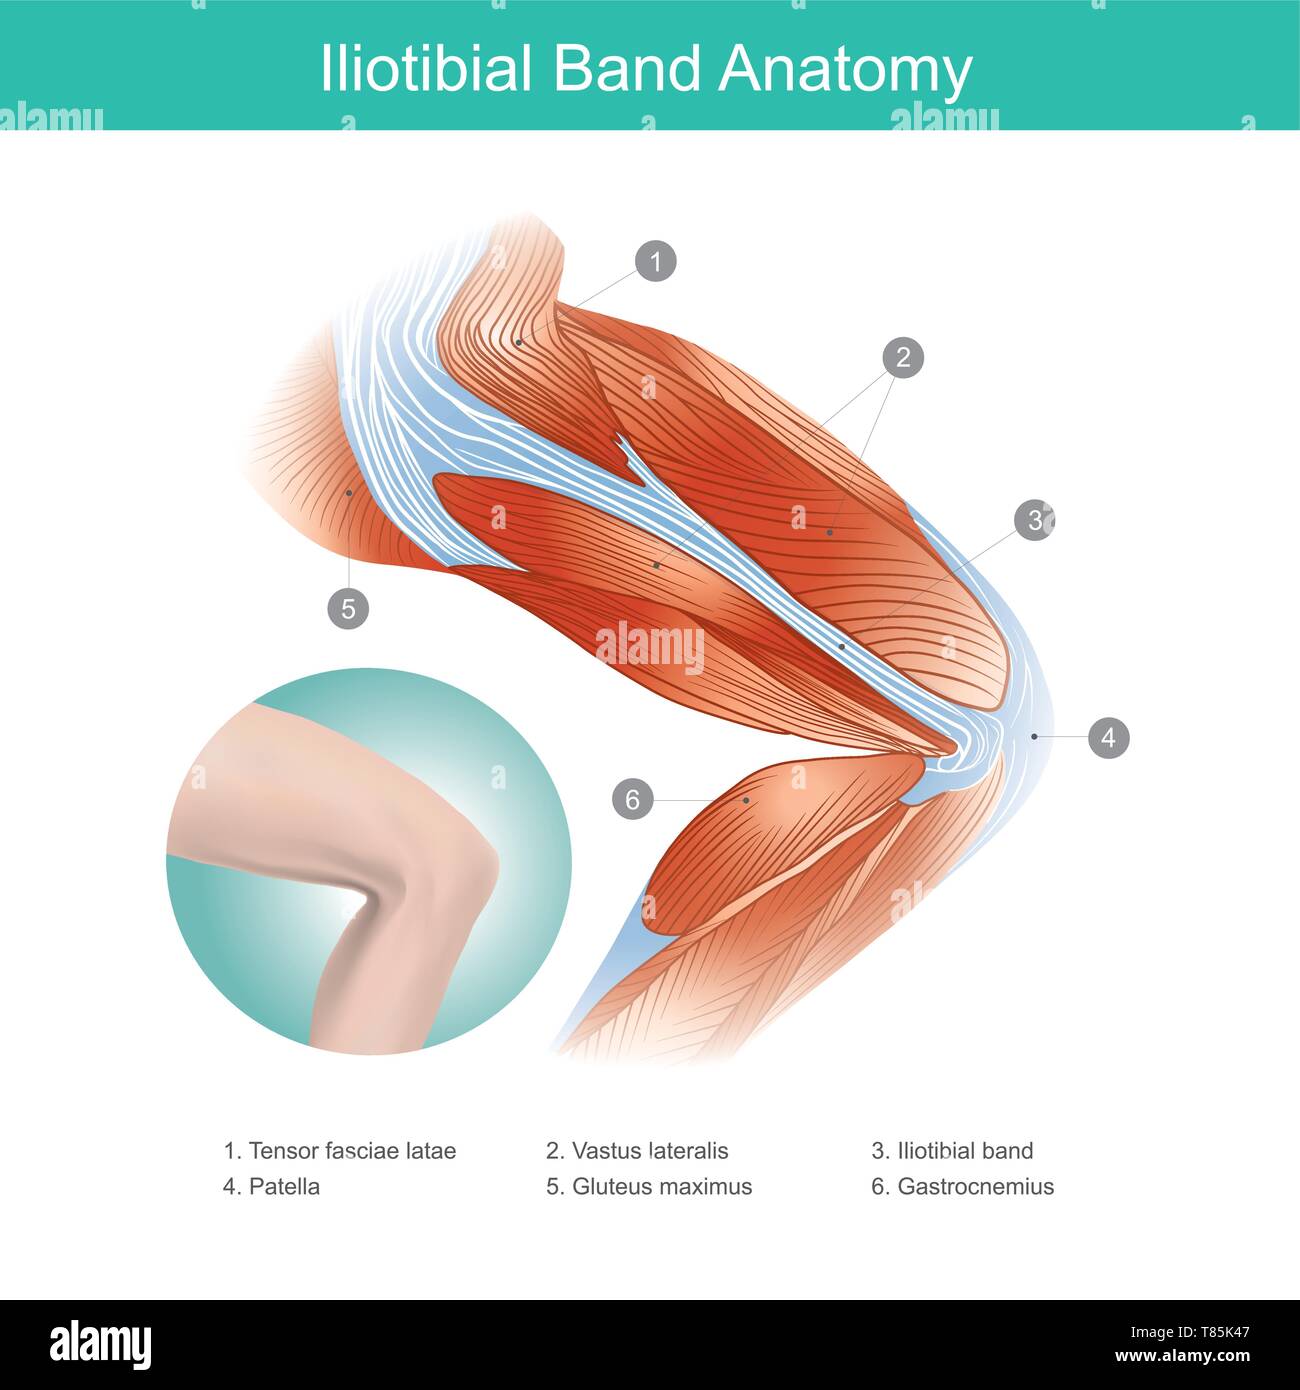

The Iliotibial Band is a longitudinal fibrous reinforcement of the fascia lata in a knee muscle. Part of anatomy human body. Illustration. Stock Vectorhttps://www.alamy.com/image-license-details/?v=1https://www.alamy.com/the-iliotibial-band-is-a-longitudinal-fibrous-reinforcement-of-the-fascia-lata-in-a-knee-muscle-part-of-anatomy-human-body-illustration-image245987192.html

The Iliotibial Band is a longitudinal fibrous reinforcement of the fascia lata in a knee muscle. Part of anatomy human body. Illustration. Stock Vectorhttps://www.alamy.com/image-license-details/?v=1https://www.alamy.com/the-iliotibial-band-is-a-longitudinal-fibrous-reinforcement-of-the-fascia-lata-in-a-knee-muscle-part-of-anatomy-human-body-illustration-image245987192.htmlRFT85K4T–The Iliotibial Band is a longitudinal fibrous reinforcement of the fascia lata in a knee muscle. Part of anatomy human body. Illustration.

The Iliotibial Band is a longitudinal fibrous reinforcement of the fascia lata in a knee muscle. Part of anatomy human body. Illustration. Stock Vectorhttps://www.alamy.com/image-license-details/?v=1https://www.alamy.com/the-iliotibial-band-is-a-longitudinal-fibrous-reinforcement-of-the-fascia-lata-in-a-knee-muscle-part-of-anatomy-human-body-illustration-image245987175.html

The Iliotibial Band is a longitudinal fibrous reinforcement of the fascia lata in a knee muscle. Part of anatomy human body. Illustration. Stock Vectorhttps://www.alamy.com/image-license-details/?v=1https://www.alamy.com/the-iliotibial-band-is-a-longitudinal-fibrous-reinforcement-of-the-fascia-lata-in-a-knee-muscle-part-of-anatomy-human-body-illustration-image245987175.htmlRFT85K47–The Iliotibial Band is a longitudinal fibrous reinforcement of the fascia lata in a knee muscle. Part of anatomy human body. Illustration.